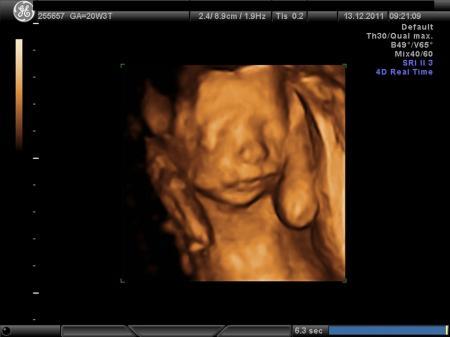

und hier das gesicht lg joline81

Bild zu